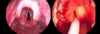

**Flexible endoscopy (laryngoscopy)** via the nose or mouth to view the larynx Rigid endoscopy if below level of larynx

66

How is laryngomalacia managed?

99% of cases resolve over time **Mild:** parental reassurance that will resolve by 12-16 months, may worsen at 6 months or during URTI **Severe:** e.g feeding difficulties, faltering growth, respiratory distress and apnoeas. Endoscopic aryepiglottoplasty aka supraglottoplasty **Life-Threatening:** Respiratory distress usually exacerbated by URTI, SEE IMAGE